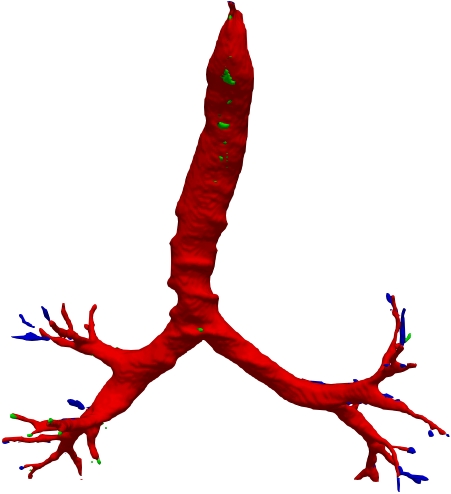

However, current state-of-the-art methods of lung organ segmentation still face several challenges and aspects for improvement. Firstly, the unlimited voxel values, multi-site imaging discrepancy and class imbalance in lung organ images can lead to false-negative and leakage issues in prior segmentation methods, which badly influences the critical early diagnosis of imperceptible lung diseases, e.g., lung fibrosis, nodule and hypertension, etc. Secondly, the presence of numerous slender branches, e.g., bronchioles and arterioles, which are easily lost during the recycled down/up-sampling procedure in Fig. 1, can result in discontinuity, detail loss, and coarse mask predictions. Thirdly, most CNN-based medical segmentation methods treat all points equally during the mask rendering stage, overlooking the vulnerability of border points in Fig. 1 (f) and the importance of explicit border modeling. Lastly, while Vision Transformer (ViT) has shown promise in computer vision tasks [1, 4], its quadratic operation complexity limits its application in 3D high-resolution CT images due to hardware constraints. Meanwhile, most specific datasets for medical image analysis are small and scarce due to laborious manual annotation and privacy protection, which badly restricts the potential of transformer-based top-tier methods.

2.2 Global-Local Cube-tree Fusion

To the best of our knowledge, most mask render-based two-stage semantic segmentation methods [6, 21] operate equally on all dense points of the coarse masks to improve the final performance, which is unnecessary to focus much on the already correctly predicted points. As shown in Fig. 1 and according to our statistical error analysis, most very vulnerable points occur on the object border due to the information loss caused by down-sample operation in the encoding process, especially for the innumerable bronchioles or arterioles in the tree-like structures. Thus, we only focus on the border vulnerable points and propose the novel global-local cube-tree fusion module. Specifically, (1) we “recycle” the down-sample and up-sample operations to produce masks and , and evaluate the absolute difference of them in Fig. 1 to get the border vulnerable points for the -th layer; (2) as shown in the top-right side of Fig. 2, we build the cube-tree of the -th point by extracting the local contextual features of {26, 27}-neighbors of the {, +1}-th layers respectively, which are defined as the cube without and with centroid. For the last layer, it is of note that we extract the 27-neighbors’ local contextual features in the adjacent layer -1; (3) we flatten features in the spatial dimension and project them as well as centroid feature into three vectors , which are separately related to the fine grain, coarse grain local context information and cube-tree centroid feature; (4) global airway or artery features from the distribution of the whole dataset is also very important, hence, we introduce the learnable global features to yield the projected global features , where is the embedding dimension; (5) we fuse the four features into as follows:

where [0, 1] are the learnable coefficients to balance the importance of each feature; (6) we lastly add the feature to the relative position embedding features (retaining the topology information for inductive bias) for the voxel-wise decoding and refined prediction. Obviously, our proposed global-local cube-tree fusion module focuses merely on all border vulnerable points in Fig. 1(f) rather than all regular dense points in Fig. 1(c), which is more related to the lung organ regions. Experimental results demonstrate the efficacy of this design.

We qualitatively analyze our method on four challenging lung organ datasets. In Fig. 5, SFCN [19] suffers from severe false positives and some false negatives, especially for the big green areas of airway leakages. WNet [22] is mainly influenced by false negatives on the main trachea. For the Fibrosis dataset at the third row, it also encounters the false negative problem in the terminal bronchioles moderately. FANN [10] bears the slight discontinuity issue of false negative in the terminal bronchioles of BAS dataset, and the severe discontinuity and airway leakage problems on the more challenging Fibrosis benchmark. Instead, due to the above two novel modules, our method can solve the defects of false negative, discontinuity, and leakages faced by past advanced methods. Besides, the results on PARSE22 artery dataset in supplementary Fig. 6 also proves this.